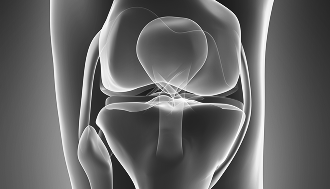

반월상연골절제 봉합술

재활 용이

빠른 회복